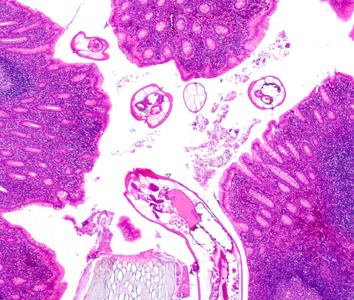

DPDx is an educational resource designed for health professionals and laboratory scientists. For an overview including prevention, control, and treatment visit www.cdc.gov/parasites/.